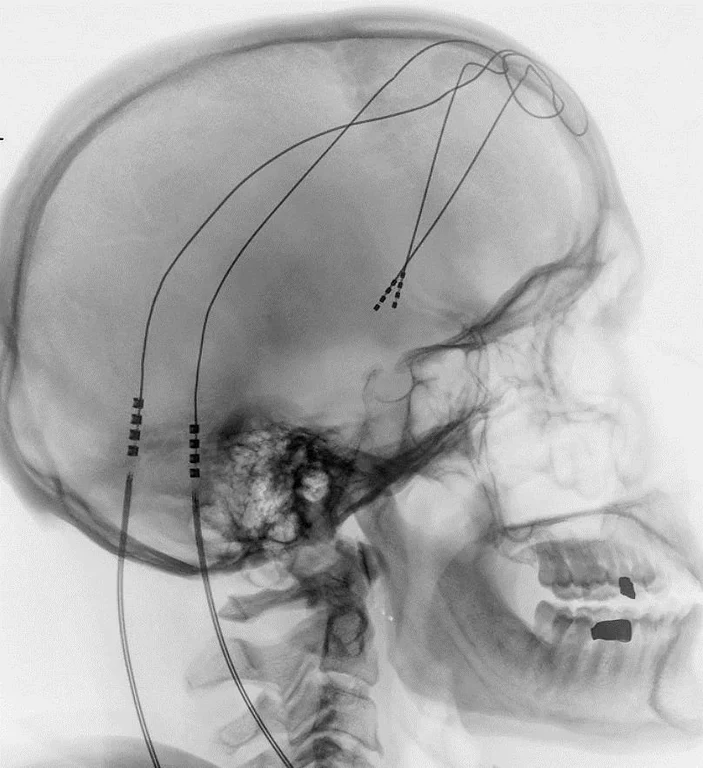

Die Mediziner implantierten Elektroden in den so genannten Nucleus accumbens ihrer Patienten. Darüber konnten sie diesen wichtigen Teil des Belohnungssystems stimulieren. In der Folge verbesserten sich die depressiven Symptome bei der Hälfte der Teilnehmer signifikant.